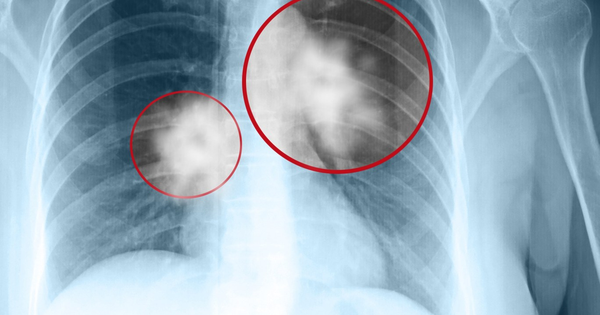

Đừng chủ quan với các nốt phổi - Dấu hiệu cảnh báo không nên bỏ qua

Nốt phổi là các vùng bóng mờ tròn có mật độ tăng cao, được phát hiện qua hình ảnh chụp cắt lớp. Dù không phải tất cả nốt phổi đều là dấu hiệu ung thư, nhưng một số loại có nguy cơ cao ác tính. Chúng được chia thành 3 loại: Nốt rắn, nốt thủy tinh mờ và nốt thủy tinh mài hỗn hợp. Trong đó, nốt hỗn hợp có xác suất trở thành ung thư cao nhất.

Đừng quá lo lắng nếu phát hiện nốt phổi, vì quá trình phát triển thành ung thư thường mất thời gian. Tuy nhiên, bạn không nên chủ quan. Nốt càng lớn thì nguy cơ ác tính càng cao. Các nốt từ 6-8mm cần được theo dõi định kỳ. Nếu kích thước lớn hơn 8mm hoặc có mật độ tăng dần, cần tiến hành các bước can thiệp chuyên sâu, kể cả phẫu thuật nếu cần thiết.